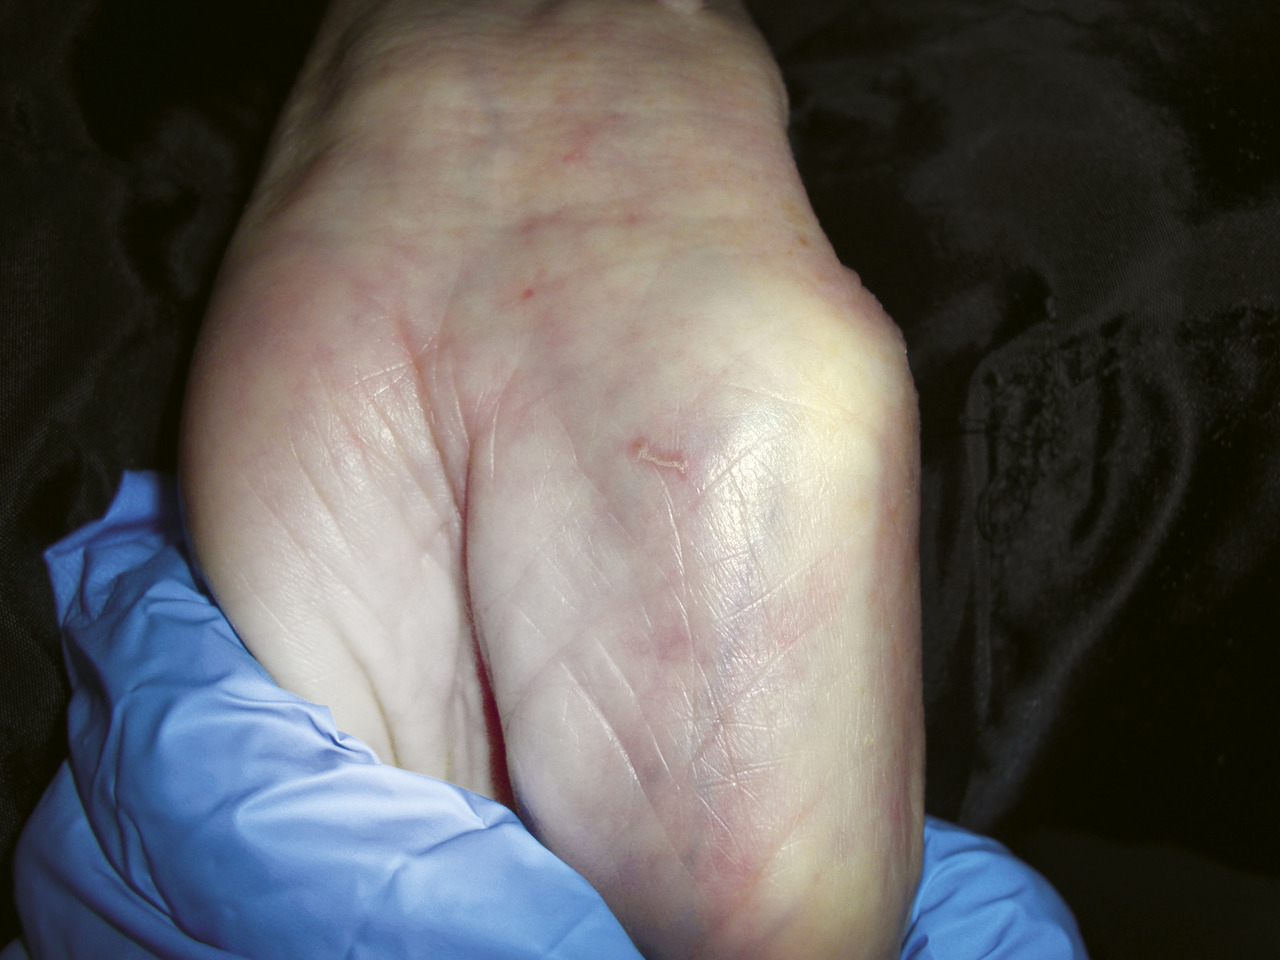

- sillons scabieux (

fig. 1 ), qui correspondent au trajet des acariens femelles. Ils prédominent au niveau des espaces interdigitaux et des faces antérieures des poignets. Longs d’une dizaine de millimètres, ils contiennent des œufs et présentent à une de leur extrémité une petite papule correspondant au siège de l’acarien femelle (éminence acarienne) ;